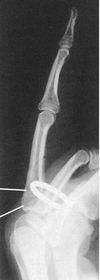

| Lateral Digit | artifact |

| What's the evaluation criteria for the Lateral finger x-ray? | ANATOMY: entire digit demonstrated CRITERIA: open joint spaces concave to one side, while the dorsal side is straight no overlapping of adjacent fingers/soft tissues POSITIONING: CR perpendicular @ PIP joint |